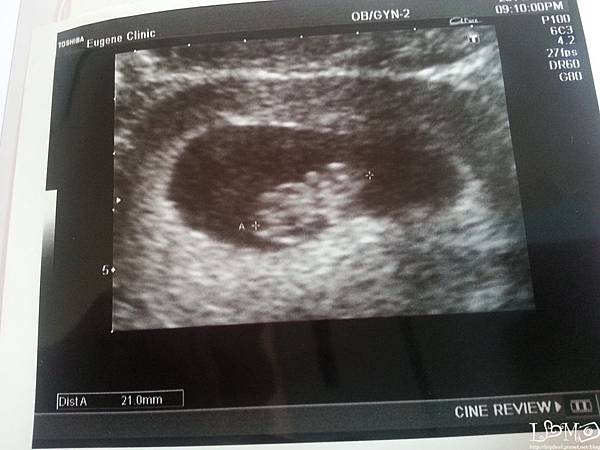

我跟惡魔在婦產科等了好久,躺在床上後,看著醫生熟練的準備照超音波

他說:長得很好ㄟ,你看這一閃一閃的是心跳,有看到嗎?

生命真的太奇妙,前一次還只是個黑點點,裡面什麼都沒有,這次遽然長孩子啦

寶寶的雛型已經有了,小心跳也很穩定的跳著

雖然醫生沒有告訴我跳多少,也沒有開聲音讓我聽(我是後來回家才查到可聽這件事)